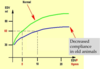

Describe Starling’s effect

To increase load, the heart automatically reacts with extra work

without hormonal/neuronal factors

Describe the heart’s work load status during rest

The heart is working in the lower range of its total working capacities

This is ensured by parasympathetic predominance